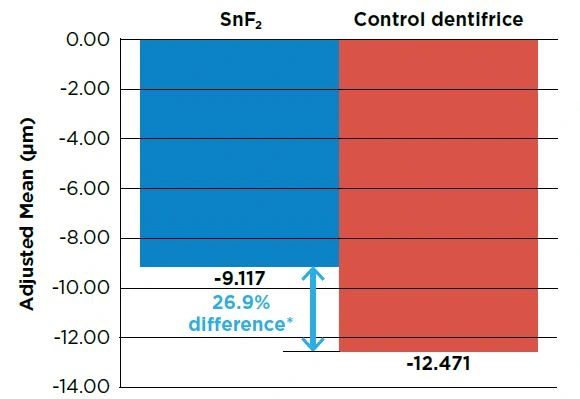

The experimental stabilized stannous fluoride (SnF2) dentifrice provided 26.9% greater erosion protection relative to the control dentifrice at Day 10 (P<0.03).

Figure. Treatment comparison at Day 10: Median Change in Enamel (μm)

To compare the enamel protection efficacy of a stabilized stannous fluoride dentifrice and a marketed control dentifrice in a 10-day in situ erosion model.

A single center, double-blind, randomized, 2-treatment, and 3-period crossover clinical study was conducted involving healthy adults.

Subjects presented for 3 study periods and were randomized to treatment sequences, receiving one of the two marketed dentifrice products each period:

Experimental 0.454% stabilized SnF2 dentifrice (Crest® PRO-HEALTH™ Clean Mint [Smooth Formula], Procter & Gamble)

Sodium fluoride dentifrice with potassium nitrate marketed for protection from the effects of acid erosion (Sensodyne Pronamel, GlaxoSmithKline)

Stabilized SnF2 dentifrice has been shown to provide significantly greater protection from acid erosion compared to other types of fluoride dentifrice.* In this trial, a novel stabilized stannous fluoride dentifrice showed a significant anti-erosion benefit over a sodium fluoride/potassium nitrate dentifrice which is marketed for protecting enamel against acid erosion. Dental professionals should consider recommending this SnF2 dentifrice for its high level of protection against acid erosion as well as its benefits for reduction of gingivitis and plaque.